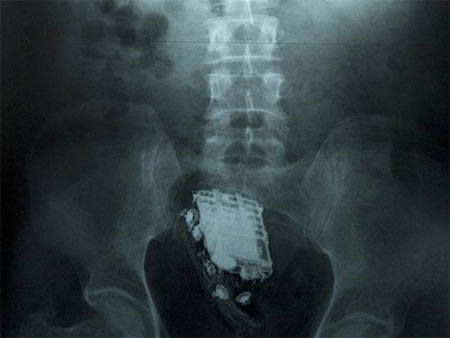

Roderick Bambury, một tù nhân đang bị giam giữ tại nhà tù Perth Prison, một trong những nhà tù được canh phòng nghiêm ngặt nhất tại Scotland, đã lâm vào tình trạng “dở khóc dở cười”, sau khi cố gắng nhét một chiếc điện thoại di động vào hậu môn với hy vọng có thể mang vào buồng giam nhưng lại không thể lấy chiếc điện thoại này ra ngoài.

Bambury sau đó đã phải trải qua một ca phẫu thuật khẩn cấp để lấy chiếc điện thoại di động ra khỏi cơ thể của mình.

Quy định của nhà tù Perth Prison là không cho phép các phạm nhân mang thiết bị liên lạc vào bên trong buồng giam. Tuy nhiên, tù nhân 36 tuổi đến từ thành phố Dundee (Scotland) thừa nhận đã sử dụng “mánh khóe” này để qua mặt các lính canh của trại giam và mang điện thoại di động vào buồng giam của mình từ tháng 6 năm ngoái.

Sau khi bị phát hiện hành vi gian lận, Bambury đã bị kết án tăng thêm 4 tháng rưỡi tù giam so với bản án phạt ban đầu.